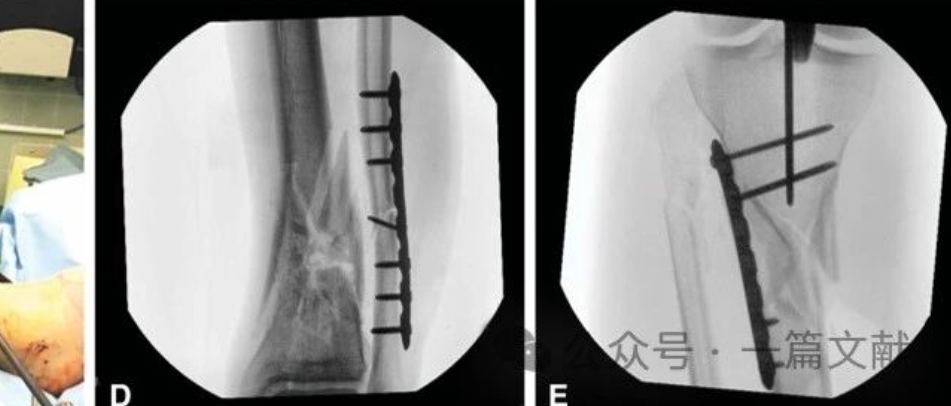

(三)耻骨支骨折

对于前环损伤表现为耻骨支骨折的不稳定骨盆损伤患者,当耻骨支骨折部位邻近耻骨体时(Nakatani Ⅰ型),即可参照耻骨联合分离处理,推荐采用Phannestiel入路钢板、螺钉内固定术。当耻骨支位于耻骨支中1/3或外1/3时(Nakatani Ⅱ、Ⅲ型),虽可采用髂腹股沟入路或Stoppa入路钢板、螺钉内固定,但在ERAS理念下,此类手术创伤大。外固定支架虽然创伤小、操作简单,但存在针道感染、松动、影响术后活动及需要定期针道护理等缺点[44]。经皮逆行或顺行长螺钉固定虽然属微创手术,但操作有一定难度,且需要较长时间放射暴露,也存在较高失效率,尤其在骨质疏松患者中[45]。而经皮骨盆内支架具有操作简单、固定可靠、不影响活动等优点[46,47]。因此对于耻骨支骨折、尤其是双侧损伤,推荐采用经皮骨盆内支架固定。也可考虑采用经皮长螺钉固定,但在骨质疏松患者中存在一定失效风险。不常规推荐切开复位。

推荐:对于需要手术治疗的耻骨支骨折,Ⅰ型骨折推荐采用Phannestiel入路钢板、螺钉内固定术,Ⅱ、Ⅲ型骨折推荐经皮骨盆内支架或长螺钉固定(推荐率:97.2%,强烈推荐率:50.7%)。